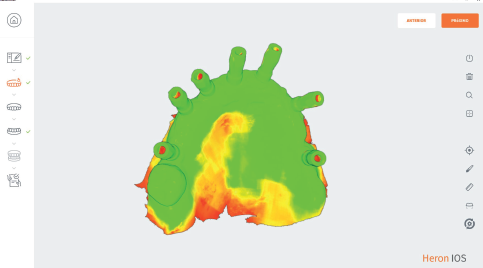

Quality Map

An exclusive tool allowing instantaneous scan quality check and live rescan if necessary to complete impression.